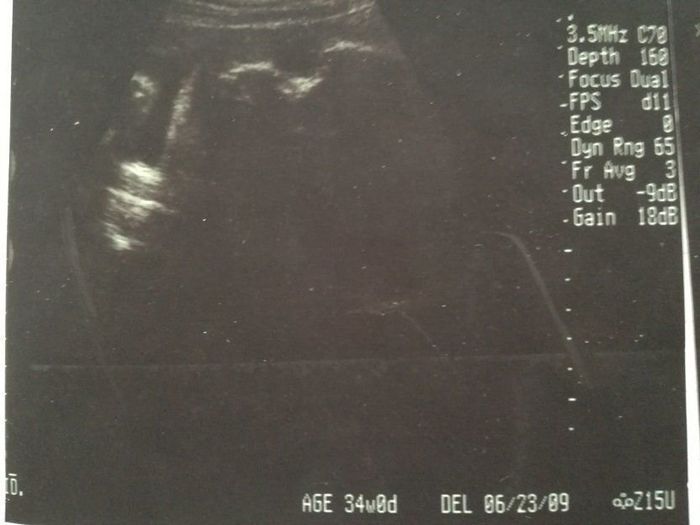

妊娠37週目のエコー写真

ついに正産期に突入で、赤ちゃんがいつ産まれてもおかしくない時期。推定体重は2700gで前よりも軽くなっていますが、「前回大きく測り過ぎた」とのことでした。「子宮口の位置がまだ高いので、すぐにはお産にならない」と言われ、のんき者の私は少し安心しました。